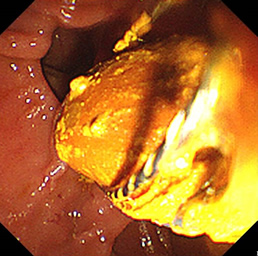

見つかったポリープ

ポリープに色素を吹きかけた状態

粘膜下層に生理食塩水を注入し、盛り上げた状態

高周波電流で粘膜下切除を行った状態

切除後クリップにて止血胃瘻造設術